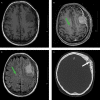

Figure 4.

Magnetic resonance imaging demonstrating a T1 isointense (a), contrast enhancing (b) dural-based lesion with a dural tail (red arrow). It is hyperintense on T2 FLAIR sequence (c). In addition, a T2 hyperintensity (green arrow) evidencing a lacune is seen in the right hemisphere (b, c), which is reflective of the common scenario of elderly patients with meningioma and comorbid cerebrovascular disease. Bone window of CT scan (d) demonstrates hyperostosis (white arrow) and osseous infiltration. These radiological features are characteristic of meningiomas.